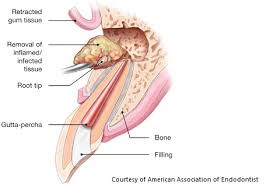

- Although there are many surgical procedures that can be performed to save a tooth, the most common is called apicoectomy or root-end resection. When inflammation or infection persists in the bony area around the end of your tooth after a root canal procedure, your endodontist may have to perform an apicoectomy.

In this procedure, the endodontist opens the gum tissue near the tooth to see the underlying bone and to remove any inflamed or infected tissue. The very end of the root is also removed. A small filling may be placed to seal the end of the root canal and a few stitches or sutures are placed in the gum to help the tissue heal properly. Over a period of months, the bone heals around the end of the root.